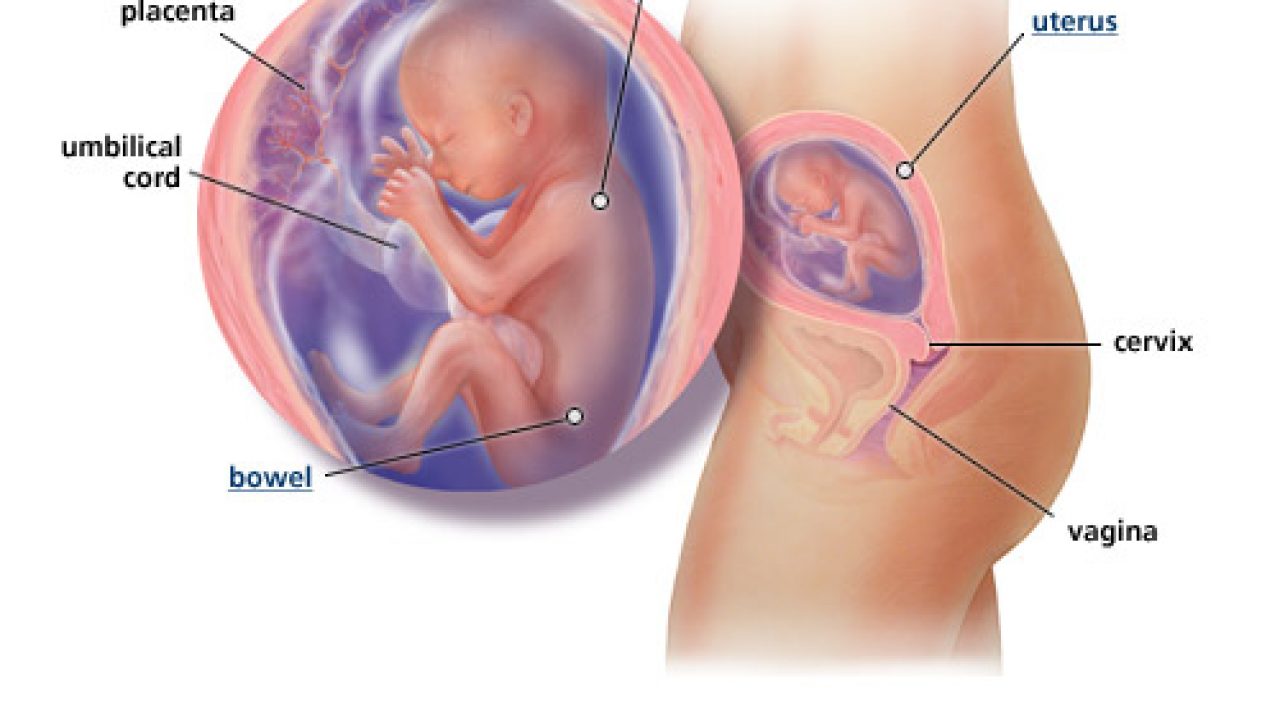

![]() Cahaya Mata Gambar Kedudukan Bayi Hamil 5 Bulan Kenapa Ibu Mengandung Mesti Berada Dalam Keadaan Selesa Dan Tenang Tulang Belakang Ibu Yang Semakin Membengkok Dan Bayi Yang Perlu Ditampung Dalam

Cahaya Mata Gambar Kedudukan Bayi Hamil 5 Bulan Kenapa Ibu Mengandung Mesti Berada Dalam Keadaan Selesa Dan Tenang Tulang Belakang Ibu Yang Semakin Membengkok Dan Bayi Yang Perlu Ditampung Dalam

Cahaya Mata Gambar Kedudukan Bayi Hamil 5 Bulan Kenapa Ibu Mengandung Mesti Berada Dalam Keadaan Selesa Dan Tenang Tulang Belakang Ibu Yang Semakin Membengkok Dan Bayi Yang Perlu Ditampung Dalam

Cahaya Mata Gambar Kedudukan Bayi Hamil 5 Bulan Kenapa Ibu Mengandung Mesti Berada Dalam Keadaan Selesa Dan Tenang Tulang Belakang Ibu Yang Semakin Membengkok Dan Bayi Yang Perlu Ditampung Dalam